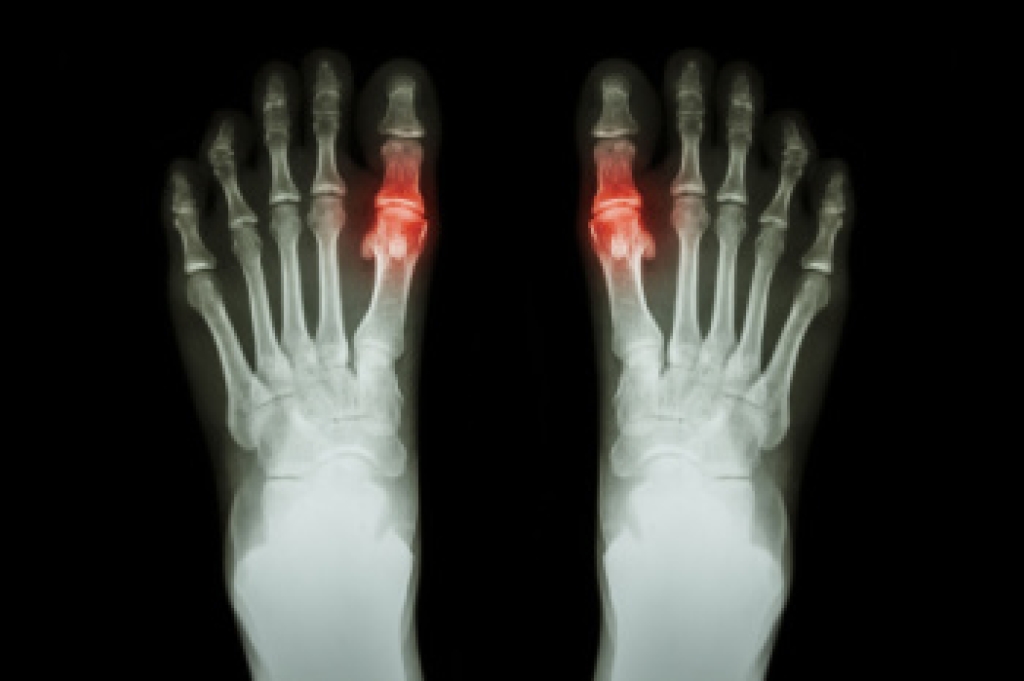

Podiatric biomechanics is a particular sector of specialty podiatry with licensed practitioners who are trained to diagnose and treat conditions affecting the foot, ankle and lower leg. Biomechanics deals with the forces that act against the body, causing an interference with the biological structures. It focuses on the movement of the ankle, the foot and the forces that interact with them.